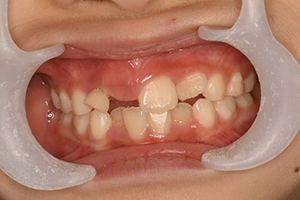

永久歯が出てくるスペースが不足

治療内容・期間 左が5歳の時の、右が7歳の時です。どちらも矯正治療前の写真です。5歳の時(左)、下の前歯2本(緑の矢印)は、左右ともにAとBの癒合歯で、2つで1つの歯になっていましたので、本数が2本不足でした。 時点でX線撮影を行ったところ、埋まっている永久歯の数は正常でした。乳歯より多い数の永久歯が出てくるためにス...